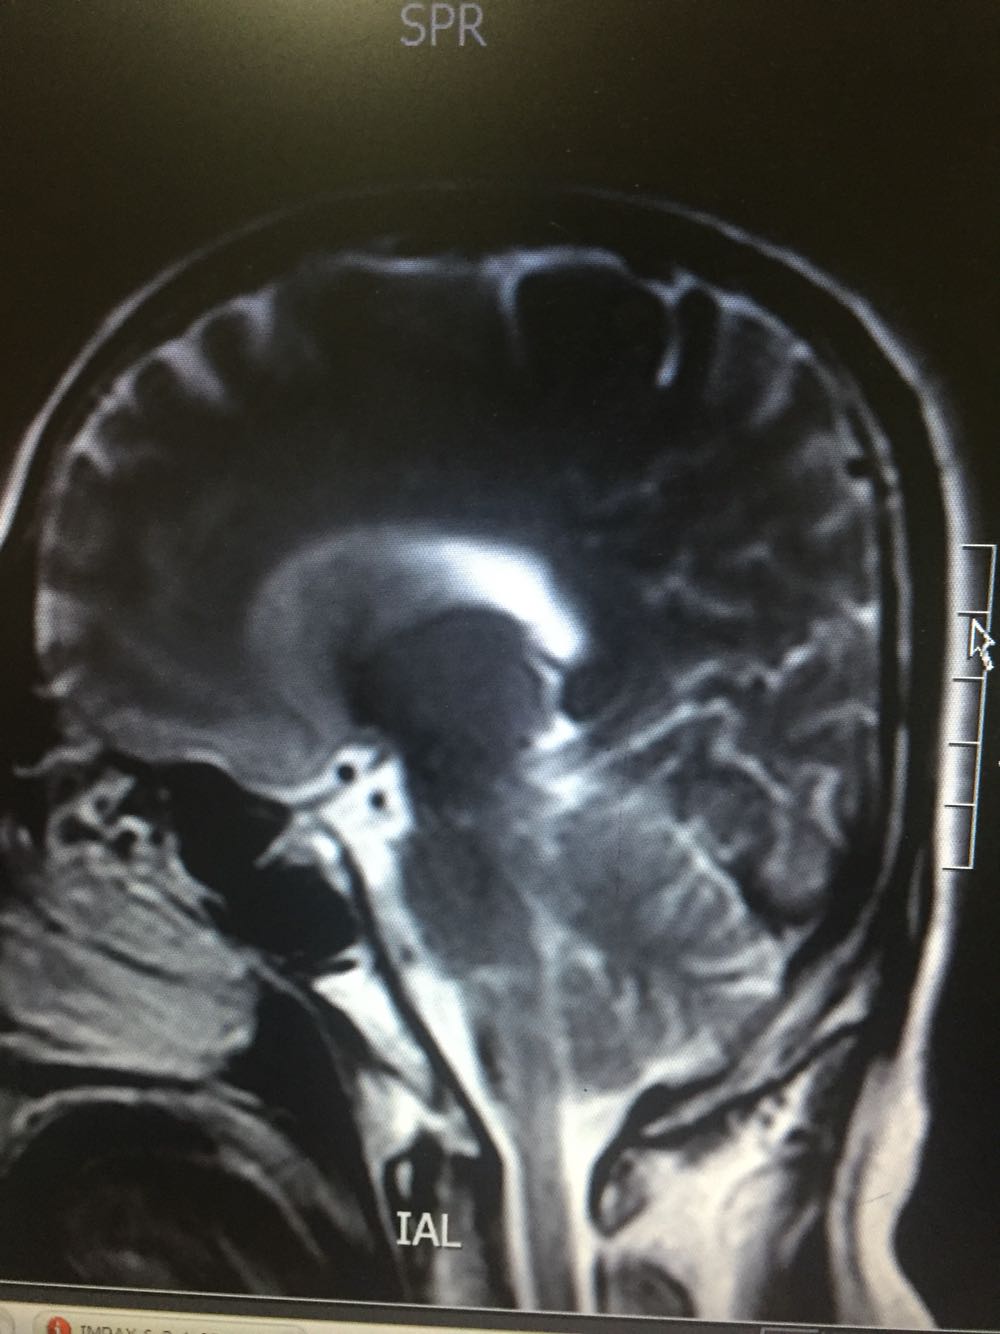

延髓梗死

54岁男患,主因左侧肢体无力伴言语含糊1日入院,既往否认高血压、糖尿病、冠心病 该患者于入院前1日吴明显诱因出现左侧肢体无力,伴有言语不清,不伴有头晕,不伴有恶心、呕吐,吴头痛,无视物旋转及视物双影,病程中无意识障碍及尿便障碍,不伴有耳鸣及听力下降,于当地医院诊断为脑梗死,静点奥扎格雷、小牛血去蛋白、血塞通、降纤酶,为求进一步诊治而来我院。

查体:血压178/102mmHg,神志清楚,构音障碍,查体合作,双瞳孔等大同圆,对光反射存在,双眼活动自如,左侧鼻唇沟浅,伸舌左偏,左侧肢体肌力3级,肌张力正常,腱反射对成,左侧感觉异常,左下肢Babinski(+)Chaddock(+),颈强(-),克氏征(-)头CT示脑梗死 甘油三酯5.69   总胆固醇6.32

延髓梗死、高血压、高脂血症 治疗改善循环、抗血小板聚集、脑保护、营养神经、调控血压、血脂对症治疗

患者存在中枢性嗝逆顽固,给予胃复安等治疗,治疗效果不佳。